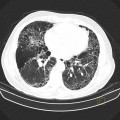

Coronavirus – COVID 19

• Opacités en verre dépoli (présentes chez tous les patients hospitalisés)

• Multiples

• Triangulaires

• Périphériques

• Bilatérales

• A prédominance basale

• Aspect de crazy paving

• Verre dépoli

• Épaississements inter et intra lobulaires

• Condensations alvéolaires

• Élargissements vasculaires au sein des lésions

• Bronchectasies par traction